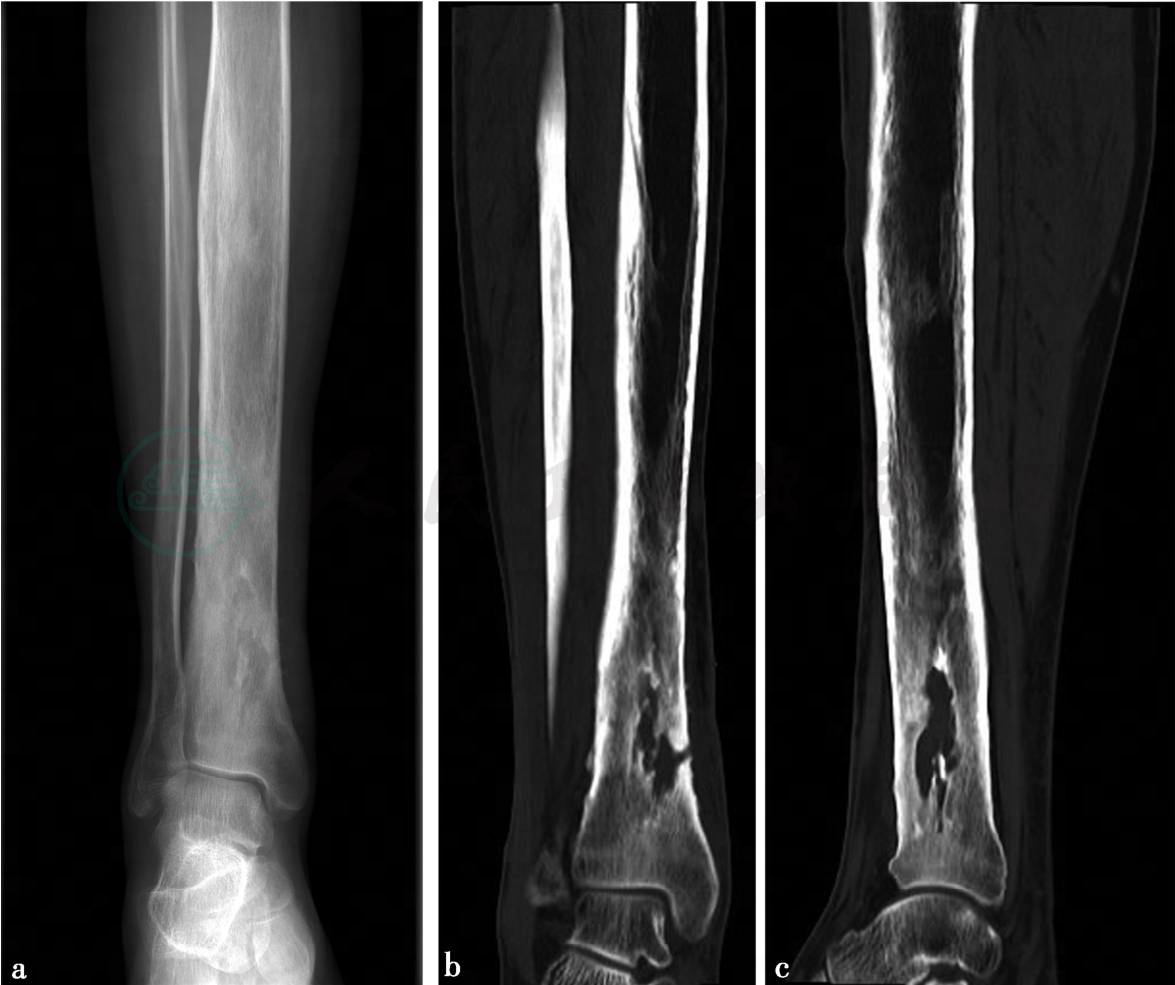

(1)病例5:

X线、CT平扫。

图1 a,X线示右胫骨中下段骨干增粗,骨皮质不规则增厚,远端骨皮质边缘毛糙。骨髓腔内密度不均匀增高,腓骨无异常,周围软组织无异常。图1b、c,CT平扫示右胫骨中下段骨干增粗,骨皮质不均匀增厚,其内侧缘局部皮质中断。髓腔内密度不均匀,可见溶骨性破坏及片状骨质硬化,病灶周围软组织肿胀